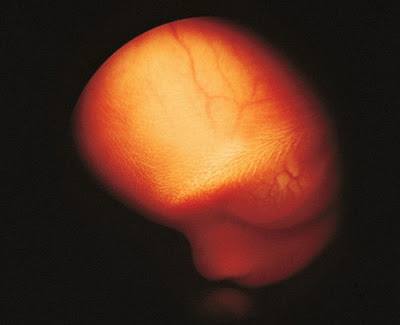

Պտուղն արդեն 16 շաբաթական է:

Բարակ մաշկի տակից երևացող արյունատար անոթները:

18-րդ շաբաթ, մոտ 14 սմ երկարություն: Պտուղն արդեն ընդունակ է ընկալել արտաքին աշխարհից եկող ձայները: